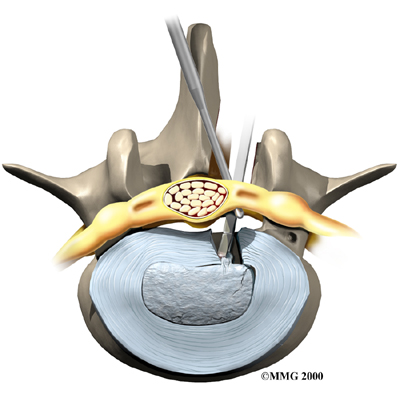

Microdiscectomy

Microdiscectomy is becoming the standard surgery for lumbar disc herniation. The procedure is used when a herniated disc is putting pressure on a nerve root. It involves carefully taking out part of the problem disc (discectomy). By performing the operation with a surgical microscope, the surgeon only needs to make a very small incision in the low back. Categorized as minimally invasive surgery, this surgery is thought to be less taxing on patients. Advocates also believe that this type of surgery is easier to perform, that it prevents scarring around the nerves and joints, and that it helps patients recover more quickly.

Related Document: FYZICAL Longview's Guide to Lumbar Discectomy